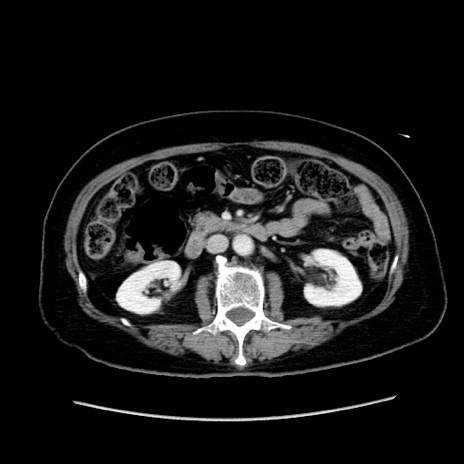

症例19(横断像)

【症例】80歳代女性

【主訴】下腹部痛

【現病歴】約8時間前より下腹部痛の出現あり、救急外来受診。

【既往歴】両側付属器切除

【身体所見】意識清明、下腹部正中に手術痕あり、その部位に一致して圧痛と反跳痛あり。腸蠕動音は亢進。

【データ】WBC 9300、CRP 0.15